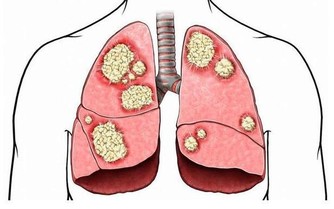

辦法:對於一些男性來說,乳房組織擴張(也被稱為男性乳房發育症)是由於睪丸激素分泌量減少和雌激素分泌量增加所引起的。一些藥物和草藥會引起男性乳房發育,某些嚴重的疾病(如癌症、甲狀腺亢進或激素功能紊亂)也會起到影響。因此一旦出現這種癥狀,應當及時就醫。